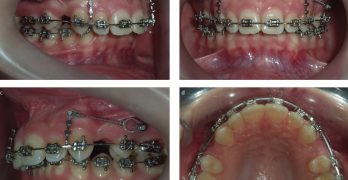

BDR CCCXII: Manejo de canino maxilar impactado con la técnica VISTA

Para terminar la semana, traemos una nota llamada Manejo de canino maxilar impactado con la técnica VISTA, en la cual … [Leer más...] acerca de BDR CCCXII: Manejo de canino maxilar impactado con la técnica VISTA